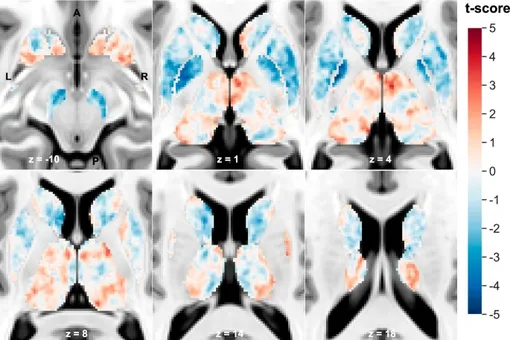

Исследователи провели магнитно-резонансную томографию мозга 85 пациентам с шизофренией и 86 здоровым людям. Более того, они использовали железочувствительное и диффузное МРТ.

В результате ученые увидели, что по сравнению со здоровыми людьми, у пациентов с шизофренией в ключевых областях было:

- снижение уровня железа;

- снижение миелина.

Эти аномалии были особенно выражены в глубоких структурах мозга, таких как хвостатое ядро, скорлупа и бледный шар, которые вместе играют важную роль в контроле движений, эмоций и сложных форм поведения.